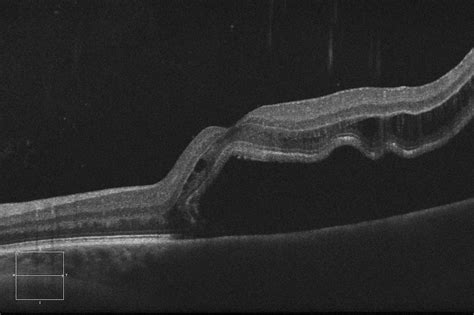

rd4 - EyeGuru